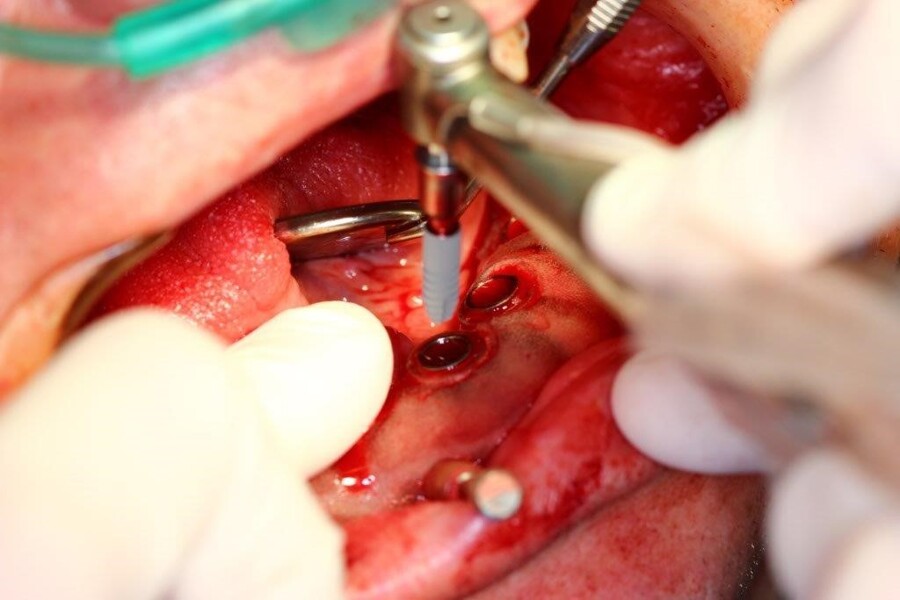

Implantacja z wykorzystaniem szablonu nawigacyjnego 3D